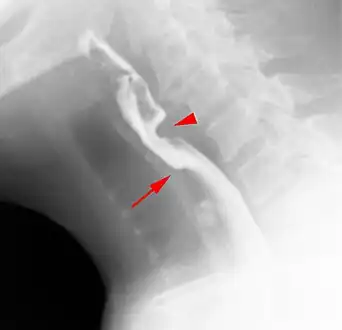

- Esophageal web stenosis in barium swallow examination lateral view.

- Web with "jet-phenomenon". Arrowhead on incomplete opening of the upper esophageal sphincter.